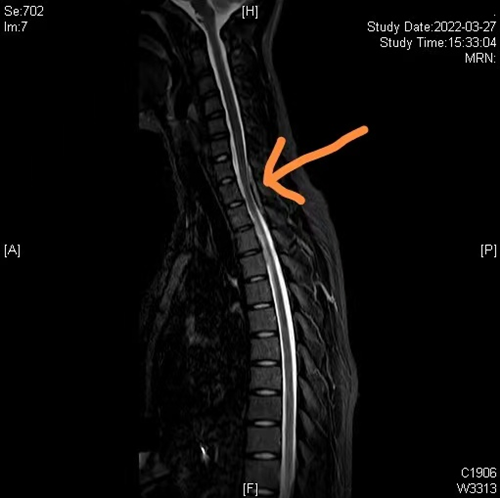

术前颈胸椎磁共振(黄色箭头提示硬膜外血肿,脊髓受压)

入院后,通过进一步完善胸腰椎磁共振等检查,证实了硬膜外血肿的诊断。脊柱外科主任、主任医师罗为民为孙温溪进行了仔细查体,发现其双下肢肌力差,感觉麻木,胸背部广泛压痛及叩击痛,没有外伤,没有感染,花季少女为什么会出现自发性硬膜外血肿、双下肢麻木?

面对患者及家属的疑问,罗为民主任介绍,这种情况临床上非常罕见,患病率大约为百万分之一,是一种以颈部或背部疼痛急性发作,伴快速进展性神经根或脊髓压迫为特征的疾病,也称为自发性脊髓硬膜外血肿,主要是由于脊髓血管发育异常所致,典型表现为突发性背部刺痛,同时有脊髓或神经受压的症状,随即发生疼痛部位以下不同程度的运动感觉障碍,严重者可发展为瘫痪,由于大部分患者病情进展迅速,常常需要急诊手术减压。对于这个女孩的治疗,罗为民建议,孙温溪诊断为颈胸段椎管内占位并截瘫,目前患者双下肢麻木没有加重,可暂时考虑绝对卧床休息、止血消肿等保守治疗;如果疼痛麻木症状加重,不排除血管再次破裂,需急诊手术治疗。

入院后前5天,经严格卧床保守治疗后,孙温溪双下肢麻木的情况一天天好转,然而到了第6天早晨,孙温溪突然出现胸背部剧烈疼痛,双下肢失去了感觉和活动功能,脊柱外科团队立即安排神经内科、神经外科等多学科会诊,制定紧急手术方案——后路颈7-胸2椎板切除、血肿清除,椎管减压术。手术非常顺利,术后当天孙温溪双下肢就恢复了部分感觉活动,经过针灸、高压氧、功能锻炼等促神经功能恢复治疗后,孙温溪的双下肢麻木症状明显缓解,目前在香港马会app康复科继续理疗训练。